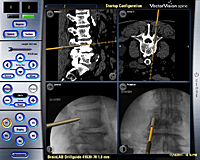

La fijación vertebral consiste en la colocación o implante de tornillos para fijar las vertebras ya sea a nivel cervical, dorsal o lumbar. La utilización de la navegación en este tipo de cirugía, que viene a ser como un GPS, permite realizar dichos implantes con un porcentaje de éxito del 97,6% evitando lesiones del nervio y re-intervenciones por mala posición de los tornillos como puede ocurrir con las técnicas clásicas. Para realizar esta cirugía utilizamos un ordenador y unas cámaras ópticas que permiten, mediante la introducción de las imágenes de una TC preoperatoria y las de unas radiografías realizadas en la posición real quirúrgica del paciente, realizar una fusión de las mismas convirtiéndolas en imágenes 3D reales-virtuales. A través de un instrumental especial, podemos visualizar en directo la trayectoria de los tornillos.

Además de la navegación en este tipo de cirugía también realizamos la monitorización de los nervios que están en relación al segmento vertebral que se interviene y a través de un ordenador obtenemos el registro eléctrico de los músculos inervados por dichos nervios. En el supuesto de una posible irritación o daño del nervio, el ordenador nos avisa mediante una descarga de ondas anormales y una señal acústica, lo cual permite rectificar la trayectoria de un tornillo evitando lesiones.